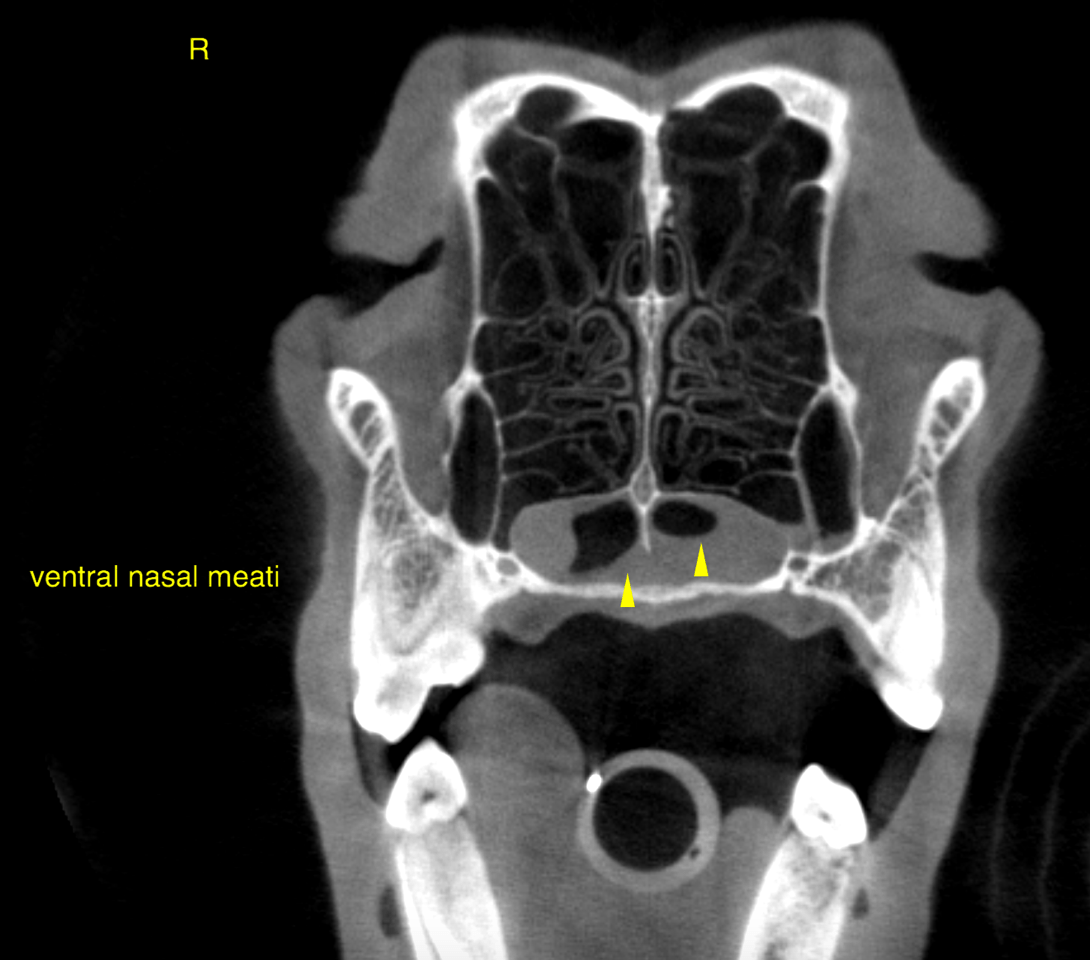

CT of the head, plain – The computed tomography reveals a moderate and mild amount of uniformly soft

tissue attenuating material in the dependent portion of the left and right nasal cavity

respectively. Part of the material is demarcated by a meniscus sign (horizontal viscous

fluid gas interface).

Mild thickening of the synovial lining and foci of mild turbinate destruction are noted

within the left nasal cavity. The overall findings are more severe on the left side.